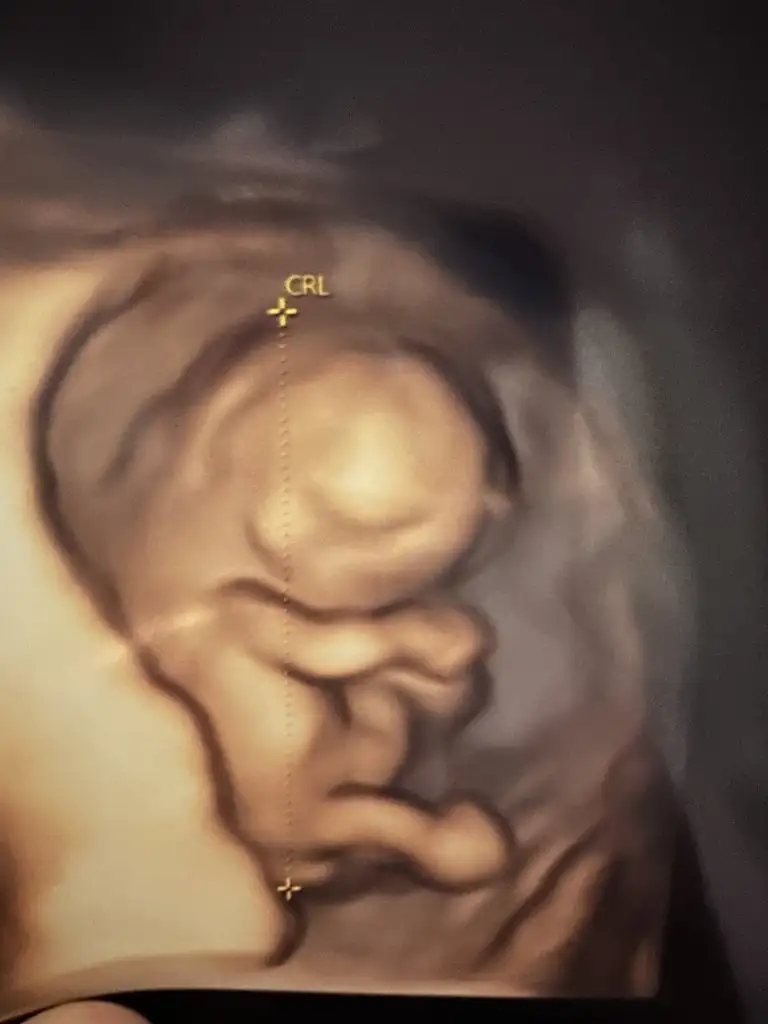

Oyyy ısırırım elini ayağını onunmerhaba teyzelerim bakın ben ne kadar pofuduk bir fındığım. Kafam gerçekten fındık gibiEllerim ayaklarım şimdiden tosbik tosbik olmuş annemle babama el bile salladım kıpır kıpırım yerimde hiç duramadım sonra da birazcık utanıp ellerimle yüzümü kapattım hehe

Bu fındık şimdilik dört gün önden gidiyormuş teyzeleri 11 haftaya uyumlu çıktı boyu posu ultrasonda anasına bir şey yedirmiyor ama depoları sağlam sömürdü demek